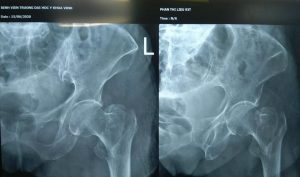

Phim chụp cổ xương đùi bệnh nhân trước phẫu thuật: hình ảnh gãy xuyên mấu chuyển